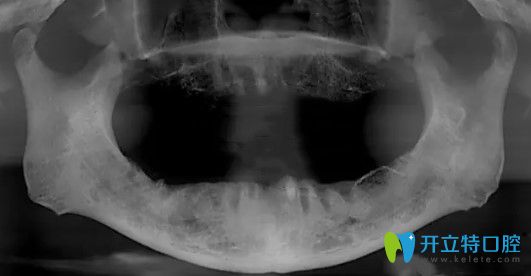

在追求美麗的道路上,一口整齊潔白的牙齒無疑是每個人的夢想。天津中諾口腔作為正規(guī)的口腔醫(yī)療機(jī)構(gòu),其正畸技術(shù)備受矚目。那么,天津中諾口腔正畸技術(shù)究竟怎么樣呢?今天,就讓我們一起走進(jìn)這家口腔醫(yī)療機(jī)構(gòu),深入了解其正畸技術(shù)的魅力!

天津中諾口腔在正畸技術(shù)上不斷創(chuàng)新,引進(jìn)國內(nèi)外先進(jìn)的正畸理念和設(shè)備,為患者提供多元化的矯正方案,醫(yī)院采用的正畸技術(shù)包括:

天津中諾口腔注重患者的個性化需求,提供多種矯正方案供患者選擇,無論是傳統(tǒng)矯正還是隱形矯正,醫(yī)院都能為患者提供滿意的解決方案。

1、個性化設(shè)計:根據(jù)患者的口腔結(jié)構(gòu)和面部美學(xué),設(shè)計專屬的矯正方案。